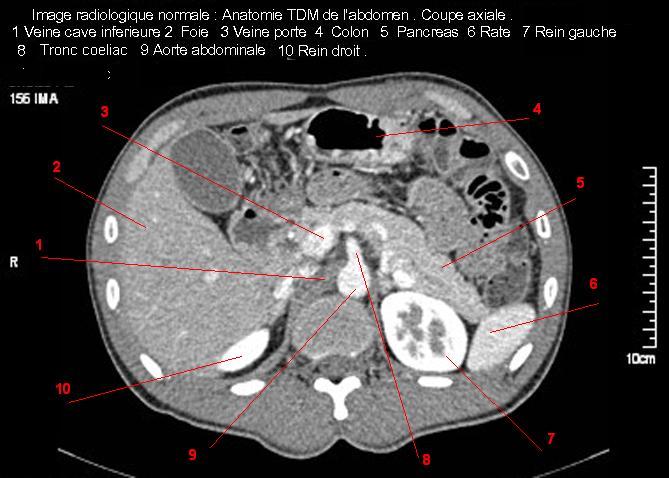

Image TDM

normale du foie :

Image TDM du foie

en coupe coronale ( axiale ) a travers tronc

portale bifurcation portale et vesicule biliaire . Double de click pour agrandir . |

|

Image TDM du foie en coupe sagitale a travers

branche droit de la veine portale , la

vesicule biliaire et le rein droit . Double de click pour agrandir . |